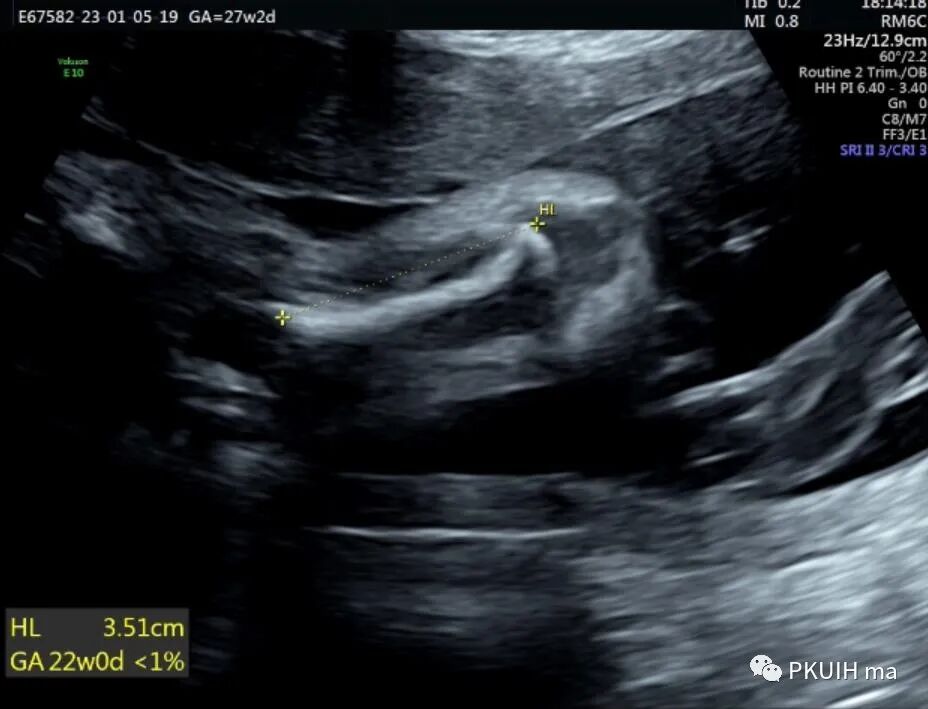

孕妇26岁,G2P0,发现胎儿肢体异常来诊,目前孕27周,超声图像如下:

四肢长骨均短缩、弯曲成角,Z值小于-4,孕妇自述第一胎也是肢体明显短,最后在当地医院引产,未做其他相关检查,本次怀孕又发现胎儿肢体短,因此来京咨询并做相关检查。

产前诊断主要依靠超声或核磁,出生后主要依靠X线和螺旋CT。超声检查建议采用连续顺序追踪法来观察胎儿肢体,如果怀疑有骨骼疾病应进行完整的胎儿超声评估,包括胎儿胎儿运动的评估。当有骨骼发育不全家族史时,应对以下超声征象仔细评估:完整的生物学测量,包括BPD、HC、AC,所有长骨的长度,股骨/足底比值,和下颌骨、锁骨、肩胛骨、颅骨、胸廓和脊柱的观察或测量。其他可能有助于鉴别骨骼发育不良的超声参数包括胎儿面部轮廓(比如鼻骨扁平)、椎体是否存在及形状、手和足的外观(比如多指(趾)、缺指(趾)或指(趾)畸形)和用来评估致死性风险的胎儿胸部。有研究显示FL/AC比值小于0.16是致死性骨骼发育不良胎儿的主要鉴别要点,并且该测值比股骨短、胸围、胸围/腹围更有效。